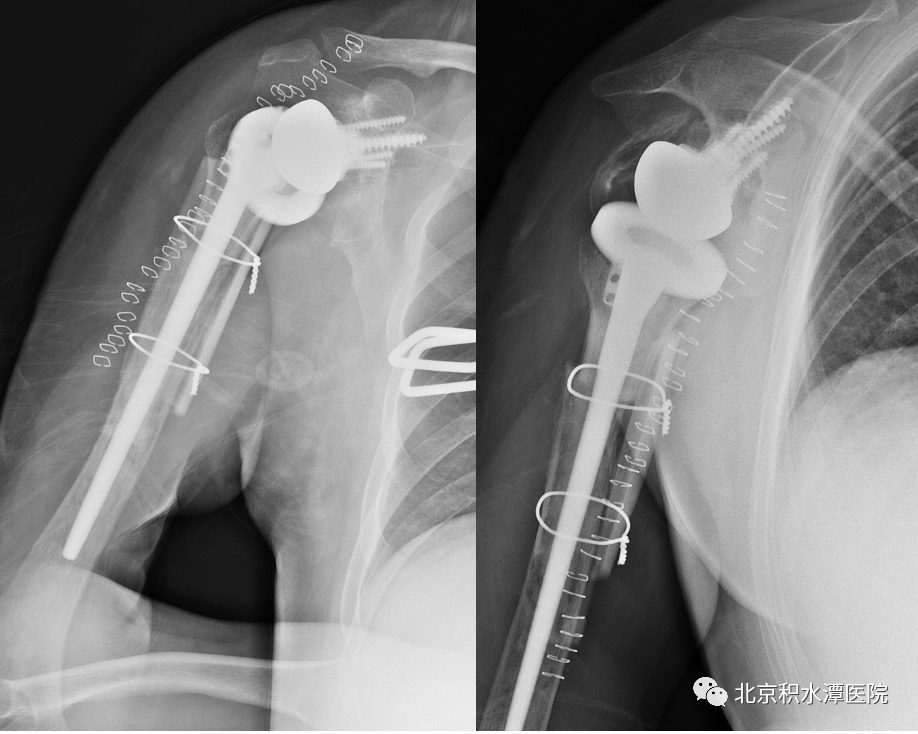

定期复查炎症指标,感染控制良好,但患者功能差,虽然带spacer无疼痛,但越来越觉得肩关节不舒服,同时想改善功能。2021年5月,患者再次回到北京积水潭医院,寻求反肩治疗改善功能。但此时患者肱骨近端大节段骨缺损、大小结节移位、肩袖组织挛缩、肩盂骨缺损严重,这种骨性状态对于反肩治疗难度很大,肩盂侧假体也无法安放与把持、现有肱骨侧假体长度不足、近端无骨性结构保护。蒋协远教授与黄强主任医师、查晔军副主任医师等讨论后,决定先为患者实行肩胛盂重建手术,并设计定制相关假体,为后期置换做准备。

术后患者复查CT,见肩胛盂骨性重建良好。但为解决现有假体长度不足的问题,此次术后,蒋协远教授、黄强主任医师就带领团队医生与工程师团队进行了反复沟通,开始设计并定制合适的反肩假体。按健侧长度计算,肱骨近端骨缺损约8厘米,起初还在肿瘤型假体和APC方式间反复讨论,最后决定采用定制反肩假体结合异体骨(APC)的方式进行处理,同时还定制了相应长度的异体骨,以更好地恢复上肢长度和三角肌张力。

2022年8月18日,患者再次回到北京积水潭医院,蒋协远教授带领黄强主任医师和查晔军副主任医师、公茂琪主任医师等为患者进行了APC反肩置换手术治疗。术中见肩胛盂骨性结构重建良好,取出螺钉,顺利安装肩盂侧反球假体。并反复通过测量和软组织张力判断,确定了异体骨长度,安装肱骨侧假体后,以异体骨板捆扎保护,手术过程顺利,拍片见肩关节假体位置满意。